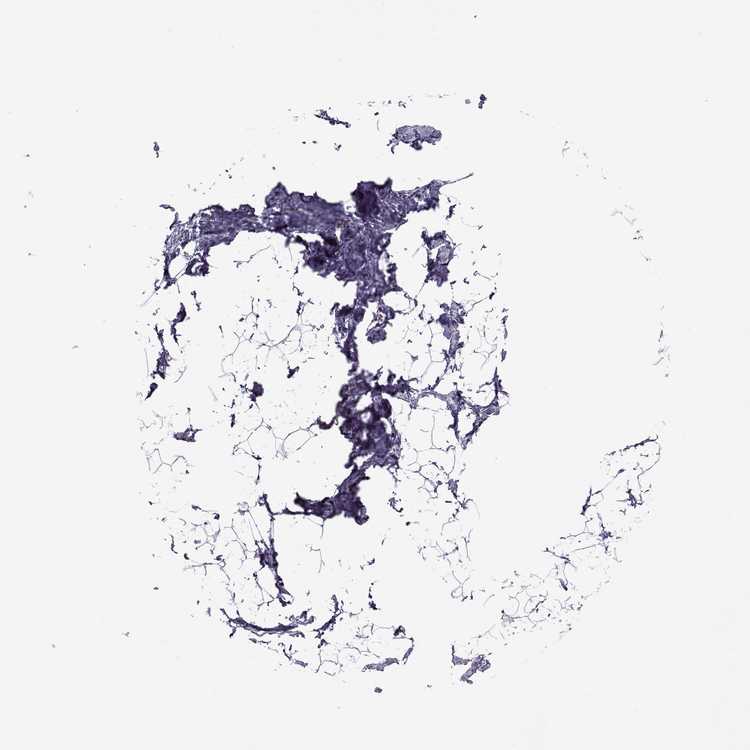

BREAST - Antibody stainingi

Antibody staining in the annotated cell types in the current human tissue is reported as not detected, low, medium, or high, based on conventional immunohistochemistry profiling in selected tissues. This score is based on the combination of the staining intensity and fraction of stained cells.

Each image is clickable and will lead to virtual microscopy that enables deeper exploration of all samples and also displays staining intensity scores, fraction scores and subcellular localization as well as patient and tissue information for each sample.

Antibody HPA077684

Adipocytes Not detected

Glandular cells Low

Myoepithelial cells Low